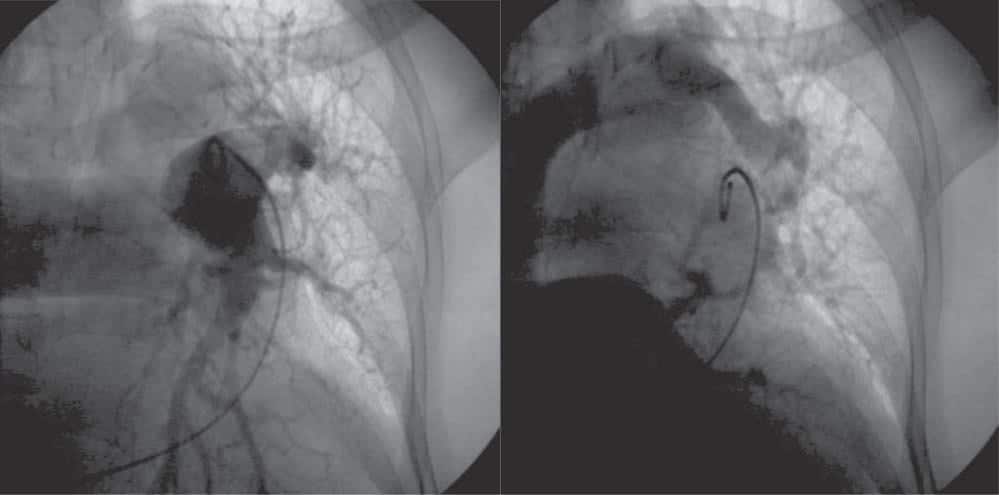

In the absence of a clear etiology to explain the PAH and its accompanying symptoms, right heart ca-theterization (RHC) was performed – this confirmed the PHT, with a mean PAP of 28 mmHg, and with a Qp/Qs higher than 1. A venous abnormality was ob-served, with the left upper pulmonary lobe draining into the left brachiocephalic vein (Figure 7). A thoracic CT confirmed and detailed the venous anomaly (Figu-re 8 and 9 – the yellow arrows indicate the trajectory of the venous anomaly).

Figure 7. Pulmonary angiography. Left: injection of contrast into the left pulmonary artery. Right: the venous network of the superior part of the left lung drains in the left brachiocephalic vein and not in one of the pulmonary veins.